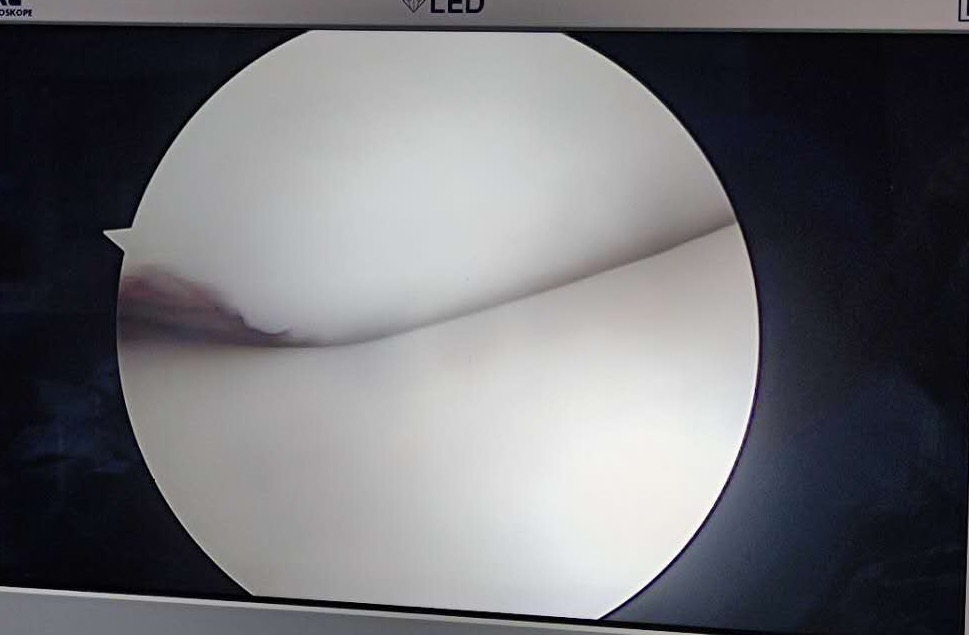

髌骨脱位造成髌骨内下极骨软骨骨折 需要CT检查 可以看见关节内游离骨片 (这是绝对需要早期手术的!)